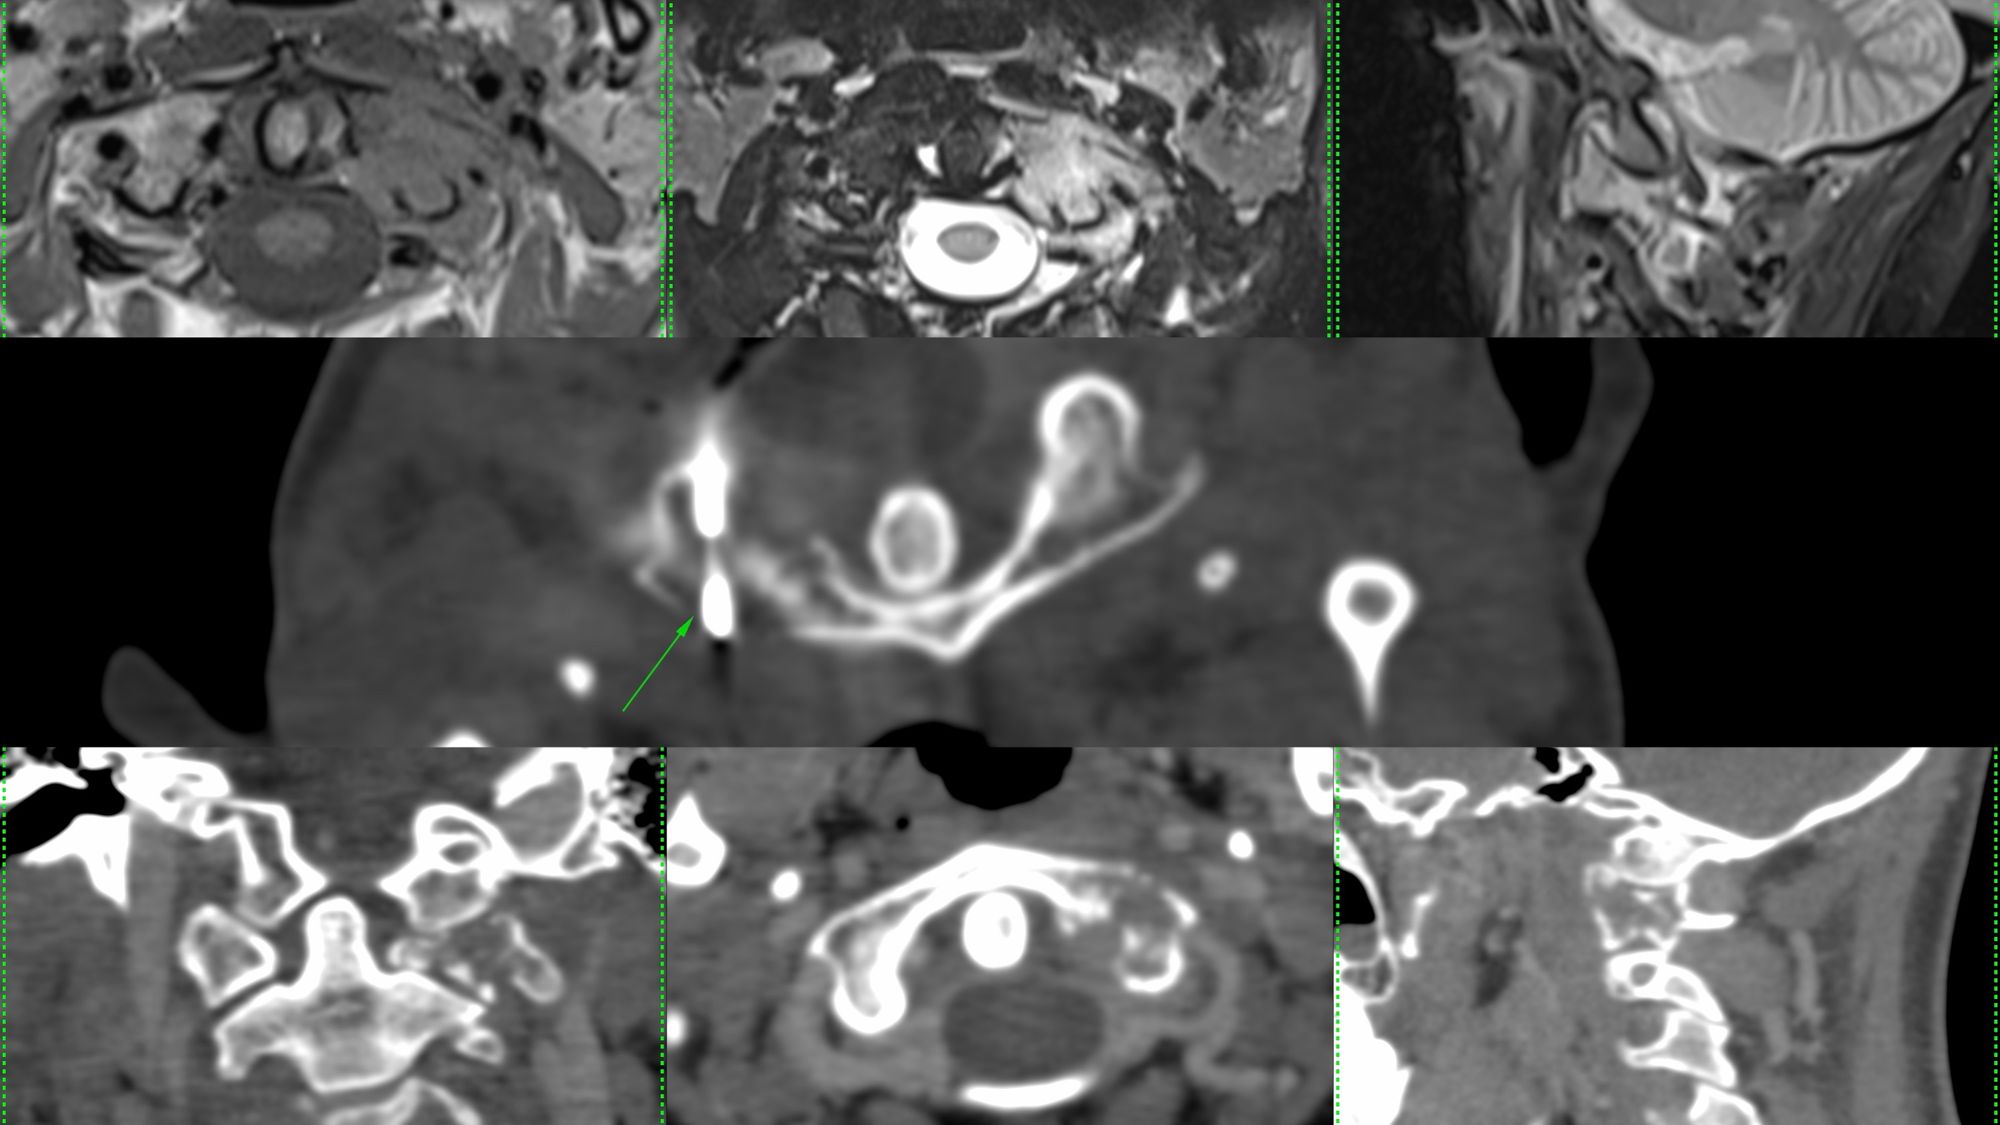

Case 55: C1 Lateral Mass Biopsy Using a Posterior Approach